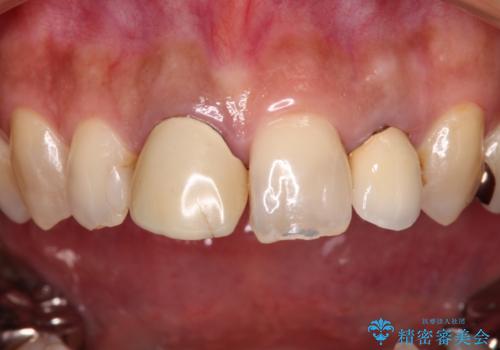

- 保険診療でのクラウンが変色してしまったとのことで来院された患者様です。

根管治療がされていなかったため、まずは根管治療を行い、その後オールセラミッククラウンにて補綴することとしました。

左上の歯も歯肉縁部分にメタルの色が見えており、合わせて治療することをお勧めしましたが、今回は1歯のみを治療することとしました。